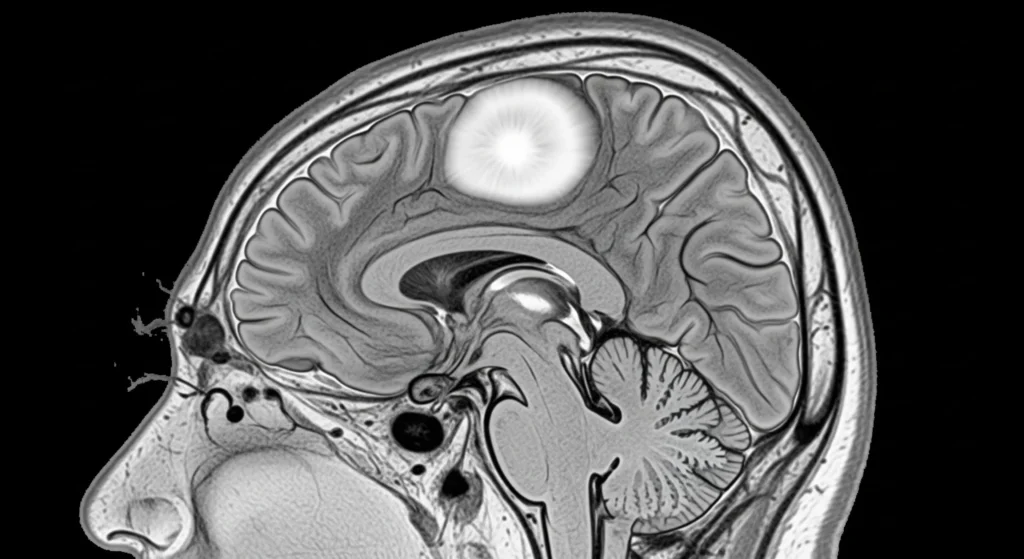

The most reliable method for diagnosing meningioma is through Magnetic Resonance Imaging (MRI).

The contrast enhancement MRI provides detailed information on tumor size, location, and its association with vital brain structures, blood supply patterns, the potential for removal surgery, etc.